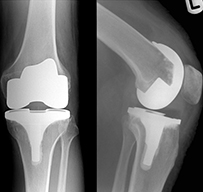

TOTAL KNEE ARTHROPLASTY

There are two main types of surgery, depending on the condition of the knee: total knee replacement and partial (half) knee replacement. A total knee replacement involves removing the damaged articular cartilage surfaces at the end of the thigh bone and the top of the tibia (the knee joint), and replacing them with a prosthetic (man-made) joint.